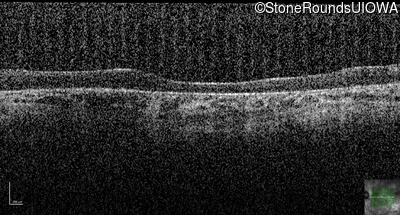

Optical Coherence Tomography - Right - 10/100 -2

Exemplar / OCT Stack